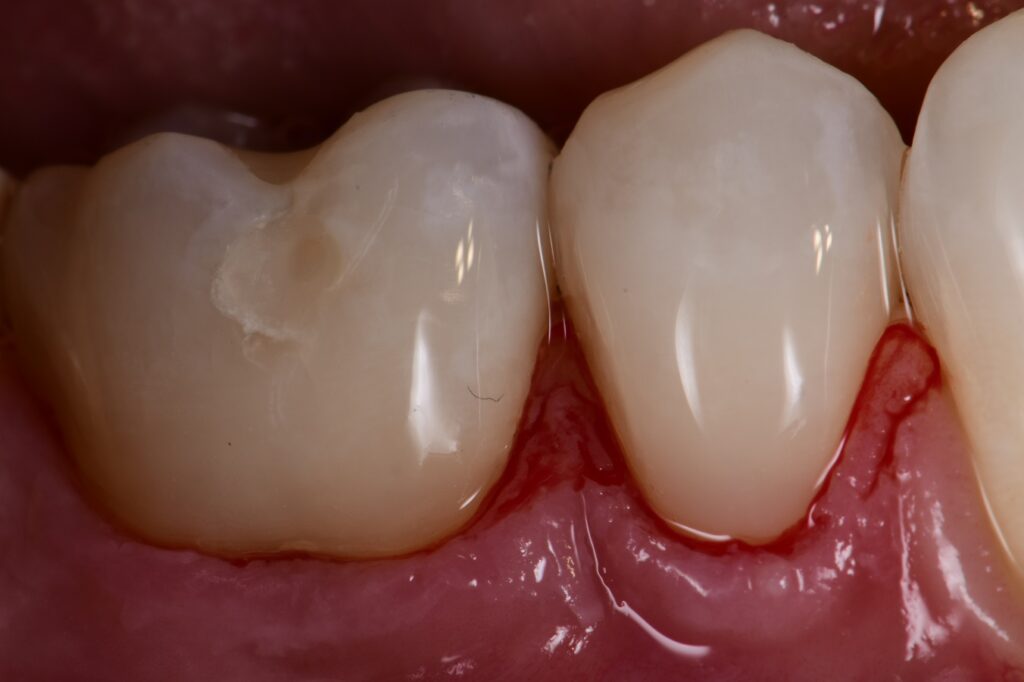

Abrasion Lesions Restored with Composite Abrasion Lesions Restored with What Is Denture Abrasion So prevention is the best way to stop. this condition, called dental abrasion, can occur when any foreign object causes friction against your teeth and gradually wears away the enamel on the surface. It can occur due to various factors, such as aggressive tooth brushing, abrasive toothpaste, bruxism (teeth grinding), and diet Some dentures replace a few missing teeth.. What Is Denture Abrasion.